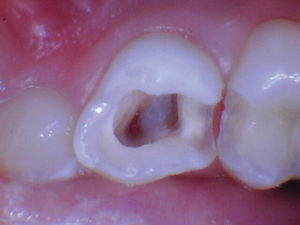

Caso 1

Un paciente de 8 años presentó descomposición de OD en un primer molar primario con síntomas de pulpitis reversible. El diente fue el tratamiento planificado para una restauración de OD con Activa Bioactive Restorative (Pulpdent). Tras la excavación por descomposición, se produjo una exposición pulpar que requirió una pulpotomía terapéutica. Debido a la edad del paciente, me sentí cómodo con una pulpotomía terapéutica con Biodentine (Septodont) seguida de una restauración estética. Si el paciente hubiera tenido entre cuatro y cinco años, me habría restaurado con una corona de acero inoxidable debido a su historial comprobado de longevidad.

Figura 2. La exposición pulpar se produjo al excavar la dentina infectada (la exposición pulpar no se capturó en la foto). |